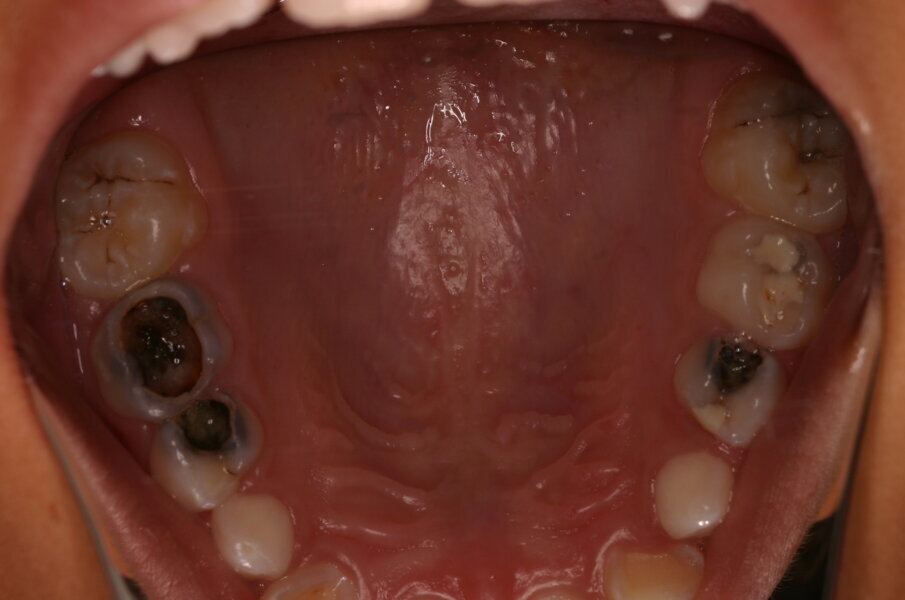

Afbeelding 6. Resultaat van de UCT-behandeling na twee jaar. De mond en caviteiten zijn schoon en het ziekteproces is tot stilstand gekomen. De ART-restauraties zien er goed uit.

Na drie en een half jaar moesten 9,1% van de amalgaamrestauraties, 9,6% van de ART-restauraties en 10% van de UCT behandelde gebitselementen geëxtraheerd worden (afbeelding 6).1 Dit verschil is statistisch niet significant en toont aan dat het schoonpoetsen van toegankelijke dentinecaviteiten en het restaureren van kleine caviteiten door middel van de ART-methode niet verschilt van het restaureren met de boor of met alleen handinstrumenten. Daarbij komt dat de UCT-aanpak minder pijnlijk was en niet meer malocclusie veroorzaakte dan de twee andere behandelmethoden.2,3 Maar wellicht de grootste winst voor de lange termijn werd geboekt bij de UCT-kinderen. Want de mate van zichtbare plaque bij blijvende elementen was na vier jaar significant lager dan bij kinderen van wie de caviteiten gerestaureerd waren.4 Zelfzorg door plaqueverwijdering met fluoridehoudende tandpasta loont en met een matige suikerinname (zie advies cariëspreventie van het Ivoren Kruis) zal het blijvende gebit lang meegaan.